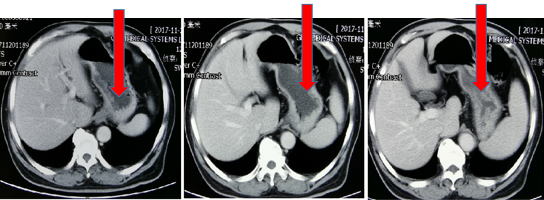

2018-11-05加入S1单药化疗,6次靶向+2周期S1化疗后,肿瘤标记物下降:CEA 947ug/L → 23.5ug/L血常规恢复正常。肿瘤明显缩小,范围变少。ECOG 1分

图3

病灶缩小,疗效评价:PR

本例患者为初诊IV期胃癌,多发肝转移,淋巴结转移,就诊我科时处于肿瘤终末状态,无手术时机并且无法耐受全身静脉化疗,遂行肝部病灶穿刺活检,送检二代基因检测提示患者ERBB2扩增,予以双靶向抗HER2治疗,2周期靶向治疗后患者肝部转移灶较前缩小且患者状态较前明显好转,ECOG评分由4分恢复至2分,继续予以双靶向抗HER2治疗2周期后,患者状态进一步好转,肿瘤标志物持续下降,肝功能好转,并有口服化疗的可能,调整方案为双靶向HER2联合口服S1抗肿瘤治疗,患者肿瘤持续缓解,患者目前带瘤生存30个月,病情平稳,持续用药。